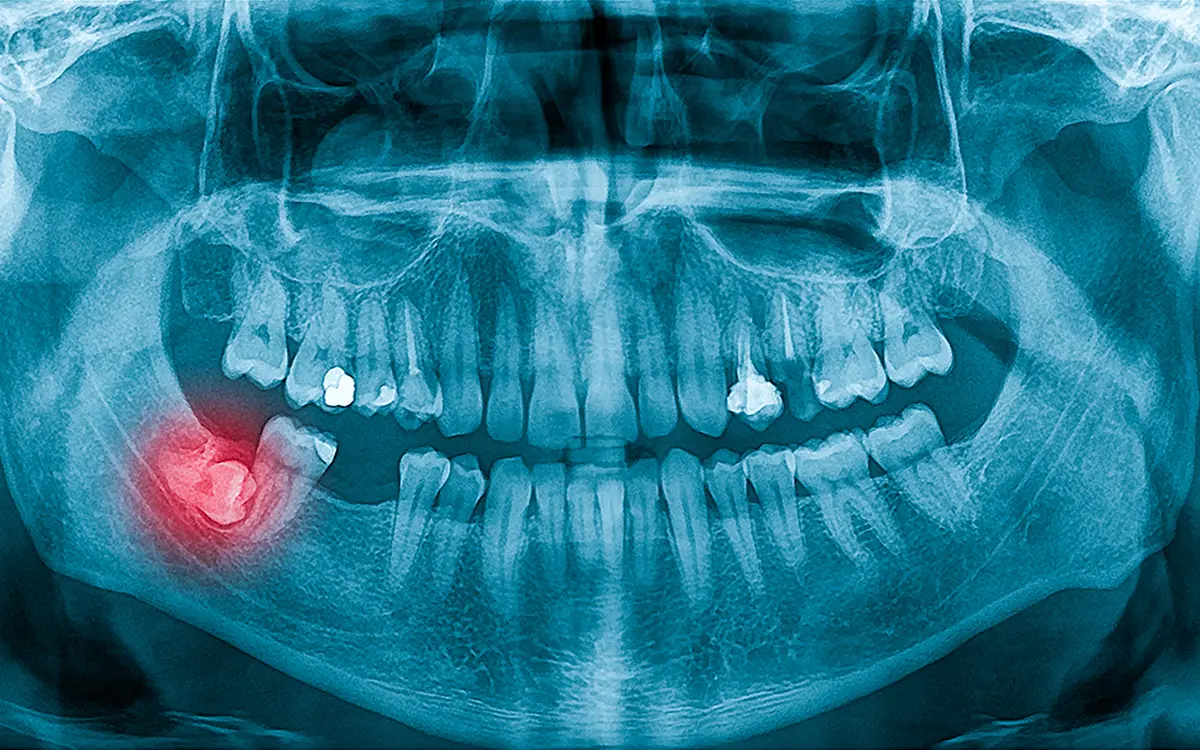

- Muayene ve Röntgen: Öncelikle panoramik röntgenle dişin ve çene yapısının durumu değerlendirilir.

- Kist ve Tümör Oluşumu: Gömülü dişlerin çevresinde oluşabilecek kistler kemik yapısını tehdit edebilir.